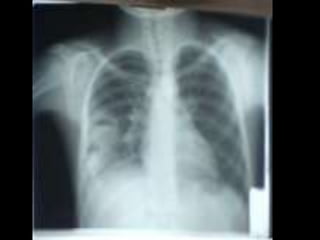

• C’est untéléthorax de face objectivant une opacité de tonalité hydrique siégeant au niveau du champ pulmonaire inférieur gauche, de forme ovalaire, mesurant 5cm de grand axe, de plage hétérogène par la présence de broncho gramme, de limites plus ou moins nettes et les contours sont irréguliers. • En appliquant le signe de la silhouette, l’opacité n’efface pas le bord gauche du médiastin donc elle est de topographie postérieure. Ailleurs on note une opacité hilaire gauche irrégulière. L’index cardio-thoracique est normal, les culs de sac pleuraux sont libres, pas de lésions osseuses visibles. • Conclusion : syndrome de comblement alvéolaire évoquant un cancer broncho-pulmonaire, métastase pulmonaire unique Diagnostic différentiel : abcès du poumon, tumeur bénigne. • CAT : TDM thoracique, échographie abdomino-pelvienne et scintigraphie osseuse Fibroscopie bronchique